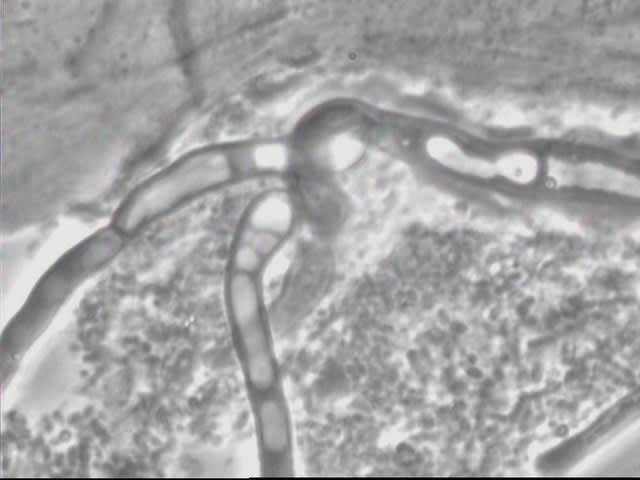

>> Et est ce que au microscope on peut voir des candidas albicans.

On peut:

Candida bourgeons gpixrn - Eugenol

Candida gxpyox - Eugenol